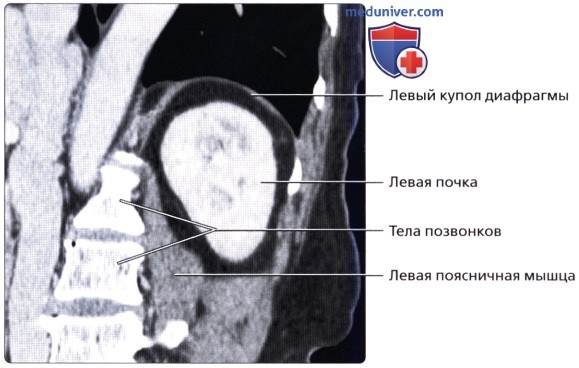

а) Анатомия почек:

2. Топографическая анатомия почки:

• Лежат в забрюшинном пространстве, окружены почечной фасцией (фасция Героты)

• У взрослого каждая почка около 9-14 см в длину и 5 см в ширину

• Обе почки лежат «на» квадратных мышцах поясницы, латеральнее поясничных мышц

б) Лучевая анатомия почки:

1. Обзор:

• Забрюшинные структуры бобовидной формы с четким контуром, смещающиеся при дыхании

о Задний эхографический доступ:

— Удобен при инвазивных процедурах (биопсия почки, нефростомия)

— Качество изображения может снижаться из-за теней от околопозвоночных мышц и ребер